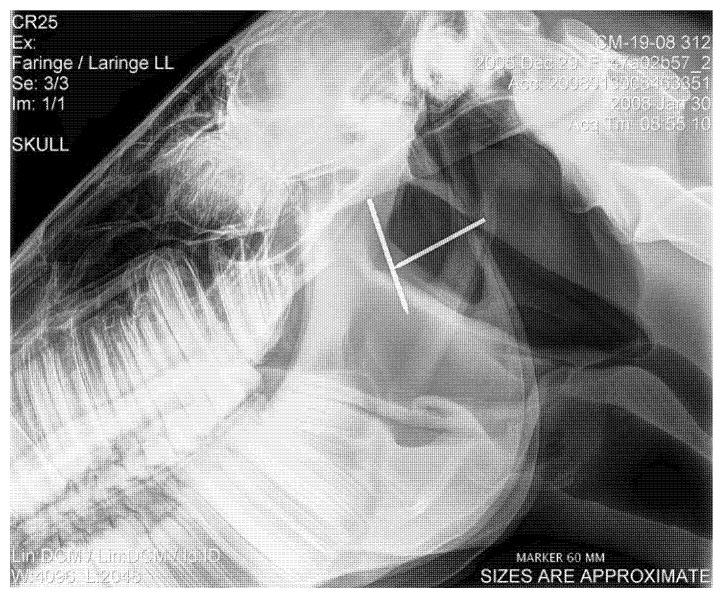

Dynamic upper airway obstructions (DUAO) are common in racehorses, but their pathogenetic mechanisms have not been completely clarified yet. Multiple studies suggest that alterations of the pharyngo-laryngeal region visible at resting endoscopy may be predictive of the onset of DUAO, and the development of DUAO may be associated with pharyngeal lymphoid hyperplasia (PLH), lower airway inflammation (LAI) and exercise-induced pulmonary hemorrhage (EIPH). The present study aims to investigate the possible relationship between the findings of a complete resting evaluation of the upper and lower airways and DUAO. In this retrospective study, 360 racehorses (Standardbreds and Thoroughbreds) referred for poor performance or abnormal respiratory noises were enrolled and underwent a diagnostic protocol including resting and high-speed treadmill endoscopy, cytological examination of the bronchoalveolar lavage fluid and radiographic assessment of the epiglottis length. In this population, epiglottis flaccidity was associated with dorsal displacement of the soft palate, while no relationship was detected between DUAO and epiglottis length. No associations were detected between DUAO and PLH, LAI or EIPH. In conclusion, it is likely that epiglottis plays a role in upper airway stability, while airways inflammation does not seem to be involved in the pathogenesis of DUAO.

动态上呼吸道阻塞(DUAO)在赛马中很常见,但其发病机制尚未完全阐明。多项研究表明,静息内镜检查时可见的咽喉区域改变可能预示着DUAO的发生,且DUAO的发展可能与咽淋巴组织增生(PLH)、下呼吸道炎症(LAI)和运动性肺出血(EIPH)有关。本研究旨在探讨上下呼吸道完整静息评估结果与DUAO之间的可能关系。在这项回顾性研究中,纳入了360匹因表现不佳或呼吸异常而转诊的赛马(标准赛马和纯种马),并对其进行了包括静息和高速跑步机内镜检查、支气管肺泡灌洗液体细胞检查以及会厌长度影像学评估在内的诊断方案。在这一群体中,会厌松弛与软腭背侧移位有关,而未检测到DUAO与会厌长度之间的关系。未检测到DUAO与PLH、LAI或EIPH之间存在关联。总之,会厌可能在上呼吸道稳定性中起作用,而气道炎症似乎未参与DUAO的发病机制。